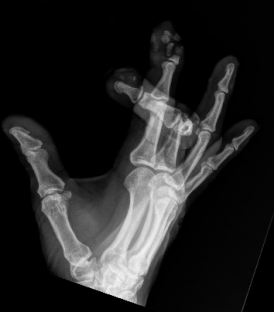

Board Review: Trauma/Orthopedics Gepost op 10 februari 20218 februari 2021 door netwerkvsseh Board Review: Trauma/Orthopedics @emdaily.cooperhealth.org Dit delen: Delen op X (Opent in een nieuw venster) X Share op Facebook (Opent in een nieuw venster) Facebook Delen op LinkedIn (Opent in een nieuw venster) LinkedIn E-mail een link naar een vriend (Opent in een nieuw venster) E-mail Afdrukken (Opent in een nieuw venster) Print Vind-ik-leuk Aan het laden... Gerelateerd